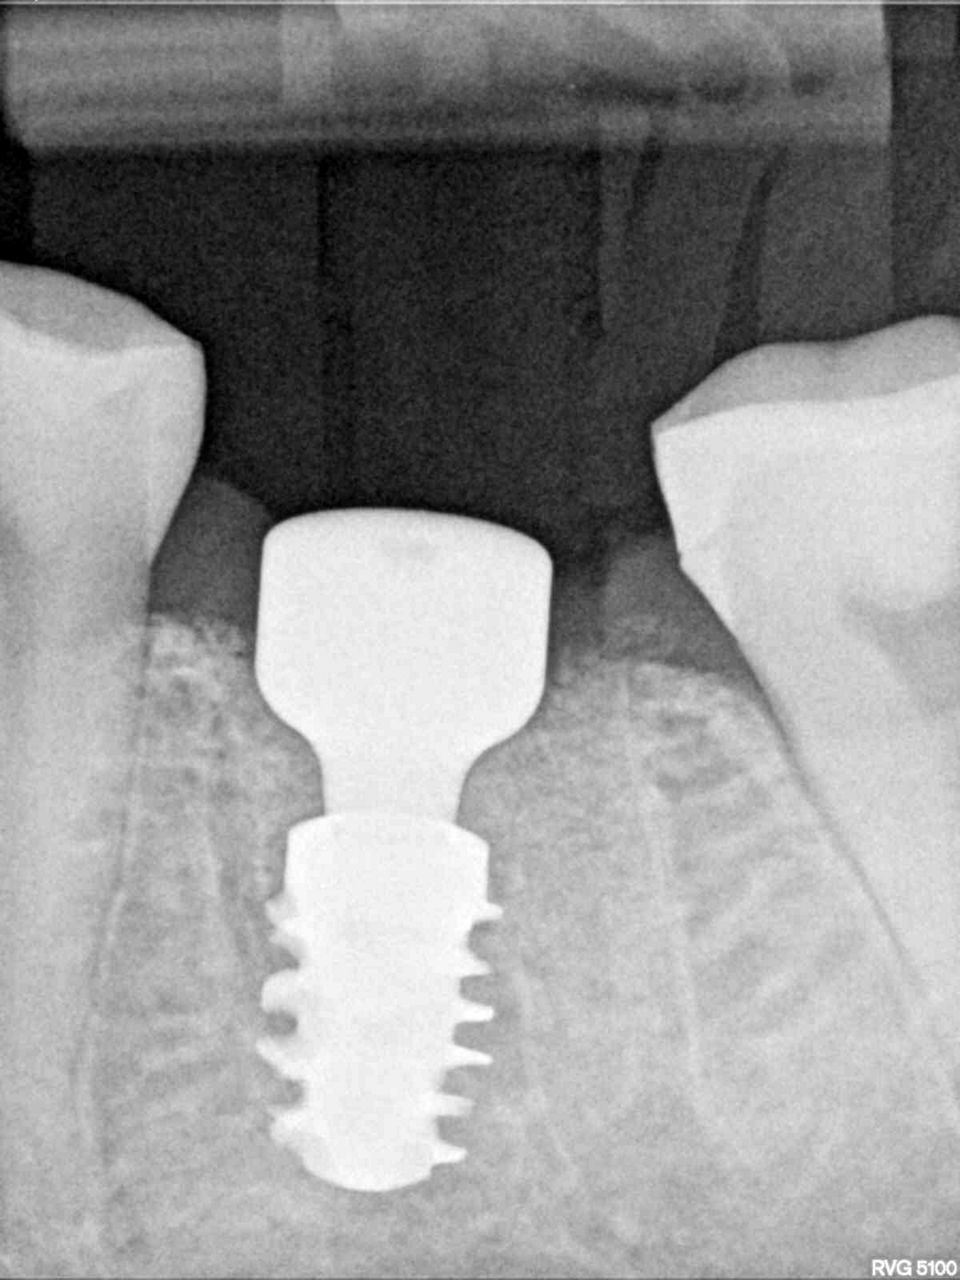

#36 牙的手术过程从局部麻醉和下牙槽神经阻滞开始。通过分割磨牙根实现无翻瓣反射的无创拔牙;从而保留肺泡壁和根间隔膜(图3-4)。仔细清洁牙槽,形成种植体路径并放置Straumann ® BLX 种植体 5.5 x 8 mm (图 5-7)。为了促进非浸没式愈合,将标准愈合基台连接至种植体。骨壁和种植体之间的间隙填充有同种异体骨材料颗粒(maxgraft®,botiss 生物材料,德国)。应用富含血小板的纤维蛋白(PRF)来实现适当的初步愈合。调整软组织边缘并用聚丙烯 6/0 缝合,使愈合基台暴露(图 8-9)。将粘性牙周Reso-Pac ®敷料(来自德国杜伊斯堡的Hager & Werken)放置在治疗区域上以协助愈合过程(图10)。

手术后一周,拆线(图11-12)。在同一次就诊时,拍摄了垂直牙科射线照片(图 13),显示种植体处于正确的修复位置。四个月后,愈合基台被移除。粘膜外观表明植入物周围有稳定且健康的软组织,具有足够的生物宽度和光滑的出现轮廓(图14-15)。取印模,一个月后,将最终的氧化锆陶瓷牙冠拧到种植体上(图 16-18)。